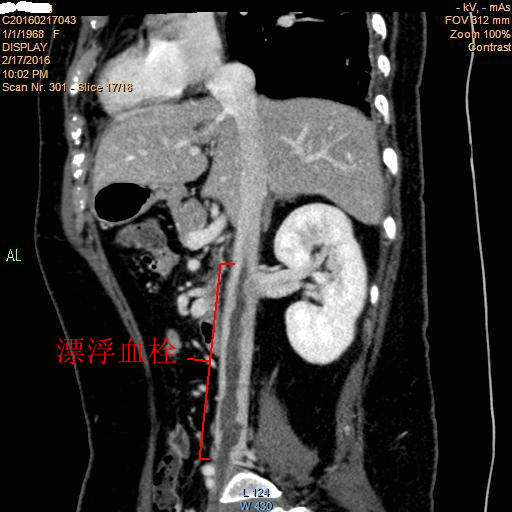

下腔静脉内漂浮血栓已超过肾静脉水平

近日,郑大五附院血管外科收治一例罕见下腔静脉内漂浮血栓形成患者。患者左下肢肿胀,脑缺氧偏瘫,下腔静脉内漂浮血栓随时都有脱落致肺栓塞可能,病情十分凶险!

我院血管外科专家王兵教授带领的治疗团队接诊后,对此罕见病例十分重视,立即与业内专家讨论、会诊。考虑到患者血栓位置较高,已超肾静脉水平,常规下腔静脉滤器无法植入,患者随时面临肺栓塞死亡风险,且血栓形态“奇特”,考虑非单纯“血栓”可能!经过反复的研究,最终决定对此例患者进行“经颈内静脉球囊封堵+下腔静脉切开取栓+下腔静脉内滤器植入术”。该手术方式较复杂,需要外科手术和介入技术密切配合,稍有不慎,下腔静脉内血栓会随时脱落导致“要命”的肺栓塞!